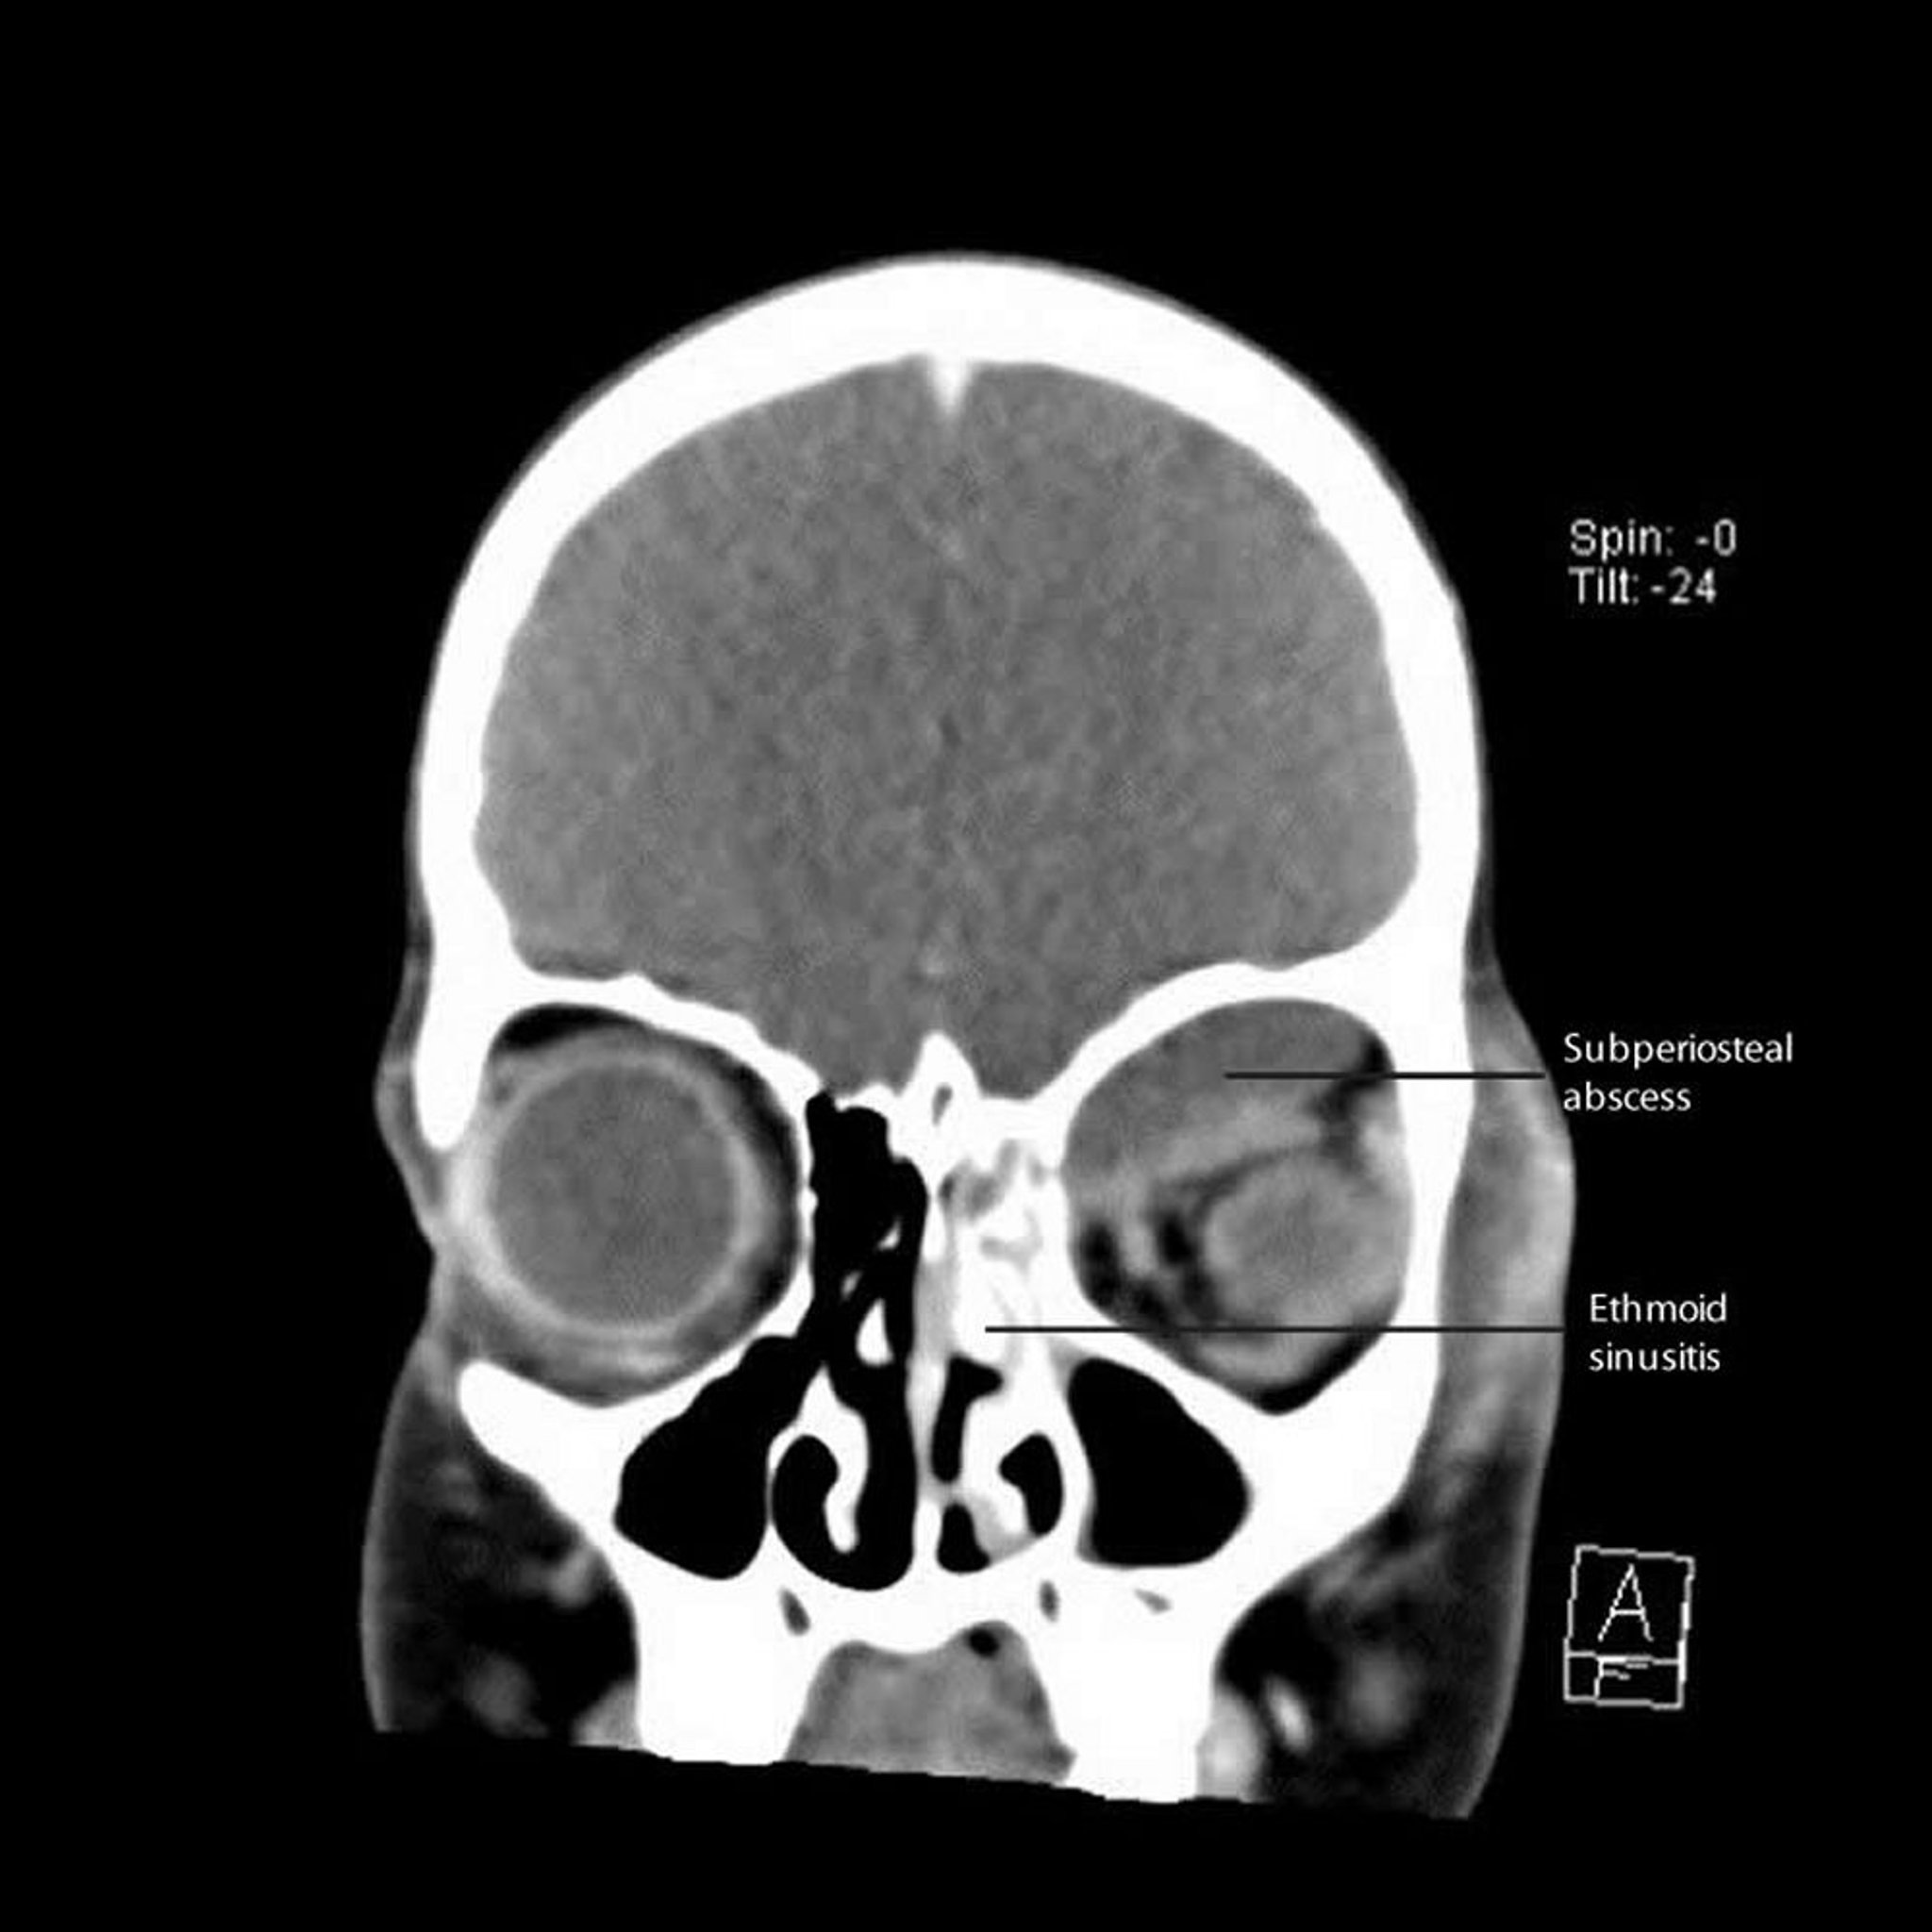

Этмоидальный синусит с субпериостальным абсцессом

На этом снимке компьютерной томографии показан левосторонний этмоидит с прилегающим субпериостальным абсцессом вдоль медиальной и верхней стенок орбиты.

CT courtesy of James Garrity, MD.